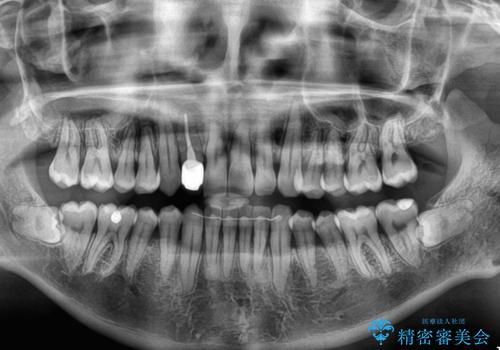

担当医としてはもう少し前歯のデコボコを改善したいところでしたが、患者様としては十分に満足いく歯列であり、マウスピース矯正に飽きてしまったとのことで、治療終了となりました。